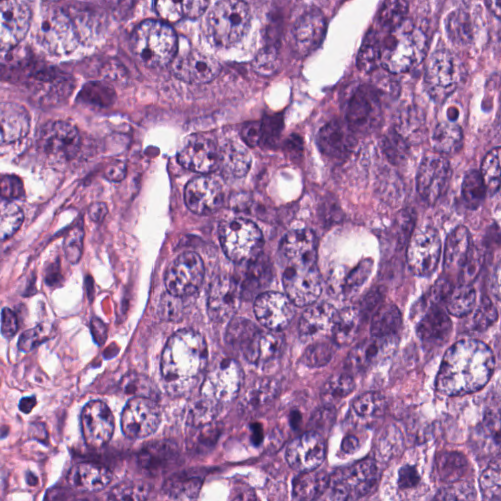

As an essential part of digital pathology, histopathology image analysis is playing increasingly important role in cancer diagnosis, which can provide direct and reliable evidence to diagnose the grade and type of cancer. This paper deals with nuclei segmentation, an important step in histopathological image analysis. The purpose of nuclei semgentation is not only counting the number of nuclei but also obtaining the detailed information of each nucleus. So unlike nuclei detection, here the outputs are the contour of each nucleus instead of only the position of their central points. Hence we can exactly extract each nucleus from the image and make it available for further analysis. For example, the features of the individual nucleus and the distribution of nuclei clusters can be used to grade and classify status of breast cancers [3, 4]. Because of appearance variation such as color, shape, and texture, nuclei segmentation from histopathological images could be very challenging, as illustrated in Fig.1, in which it is very challenging even for human to recognize and segment all nuclei within the images. Fig.1(a) and Fig.1(b) illustrate two histopathological images from different organs. Fig.1(c) and Fig.1(d) are two histopathological images from same organ but have different cancer grade.